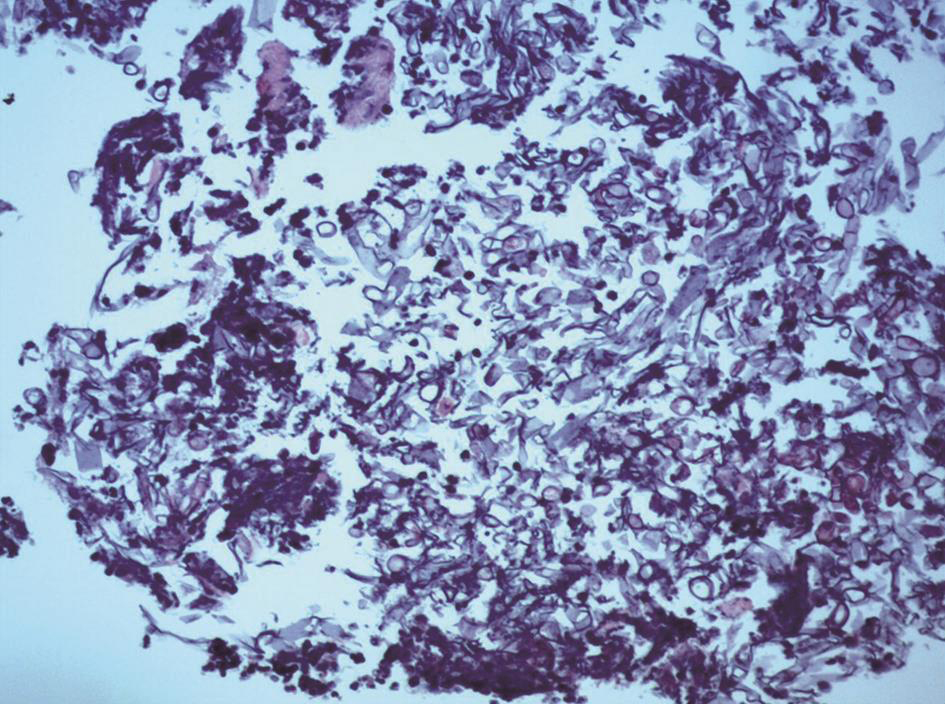

支气管镜检查:右下前基底支气管(EBUS-GS-TBLB)穿刺活检组织内见真菌菌丝及孢子,形态较符合毛霉菌伴黏膜慢性炎(图4)。

图4 肺活检组织病理学表现

活检组织中见毛霉菌菌丝宽大、无分隔,呈直角分支(HE染色,400×)